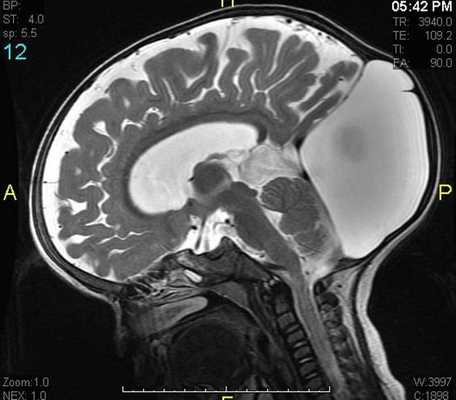

Пинеальная киста расположена в проекции шишковидной железы. Встречается с частотой 4-11%. Размеры обычно не превышают 1 см, но изредка встречаются больших размеров. В таких случаях она вызывает окклюзионную гидроцефалию. При головного мозга она имеет все признаки кисты с примесью белка в жидкости, то есть немного светлая на Т1-взвешенных. Изредка встречается геморрагическое содержимое. Киста может контрастироваться по периферии.

Пинеальная киста расположена в проекции шишковидной железы. Встречается с частотой 4-11%. Размеры обычно не превышают 1 см, но изредка встречаются больших размеров. В таких случаях она вызывает окклюзионную гидроцефалию. При МРТ головного мозга она имеет все признаки кисты с примесью белка в жидкости, то есть немного светлая на Т1-зависимых МРТ. Изредка встречается геморрагическое содержимое. Киста может по усиливаться периферии при МРТ головного мозга с контрастированием.

МРТ головного мозга. Т1-взвешенная сагиттальная МРТ. Пинеальная киста.